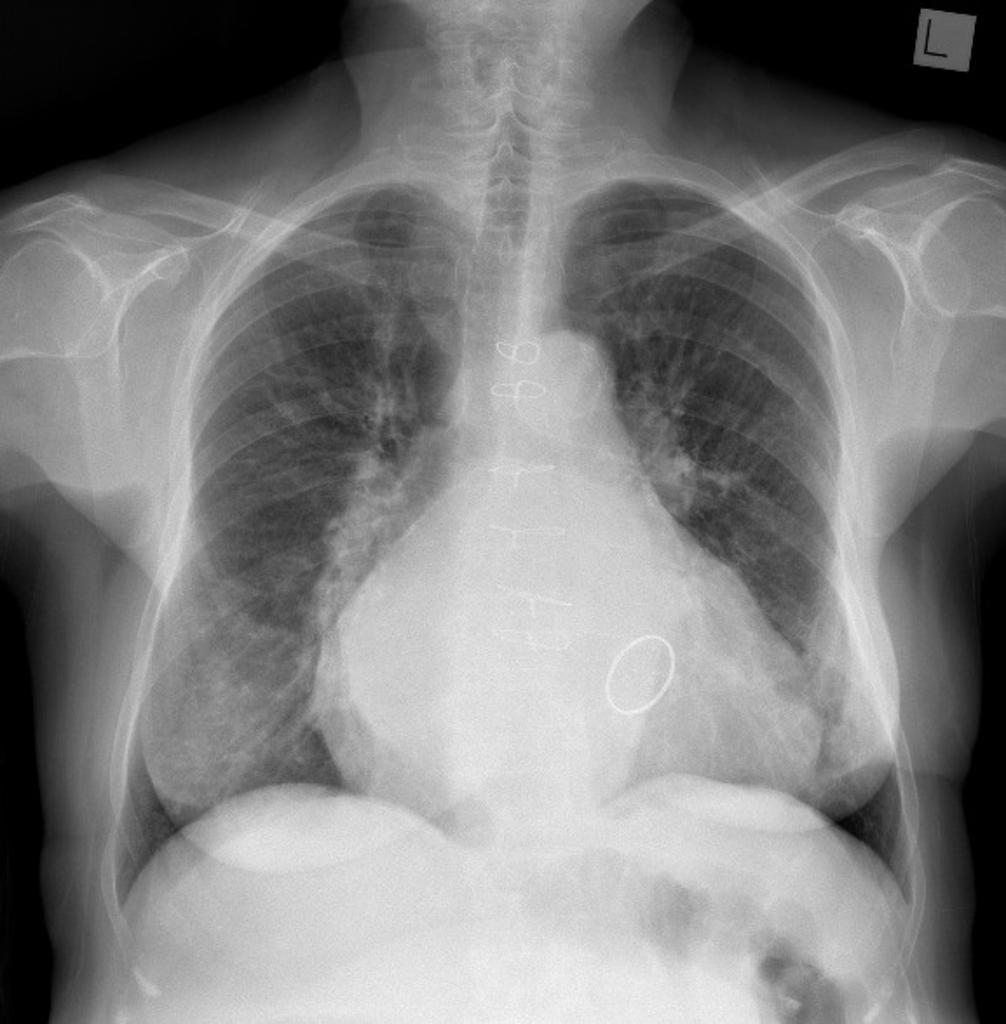

Pneumonia

But where?